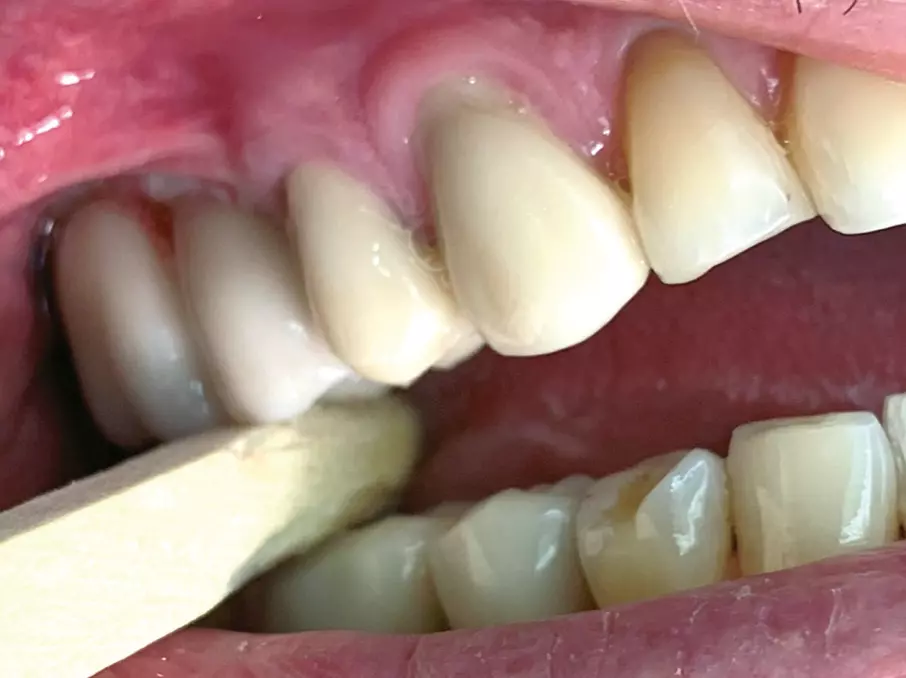

Der Praktiker schätzt vor allem im distalen Bereich das einfache Einsetzen der Rekonstruktion ohne Manipulation mit einem Schraubendreher. Der Patient wird aufgefordert, fest auf einen Holzspatel zu beißen, um die Reibhaftung zu aktivieren (Abb 8a-c).